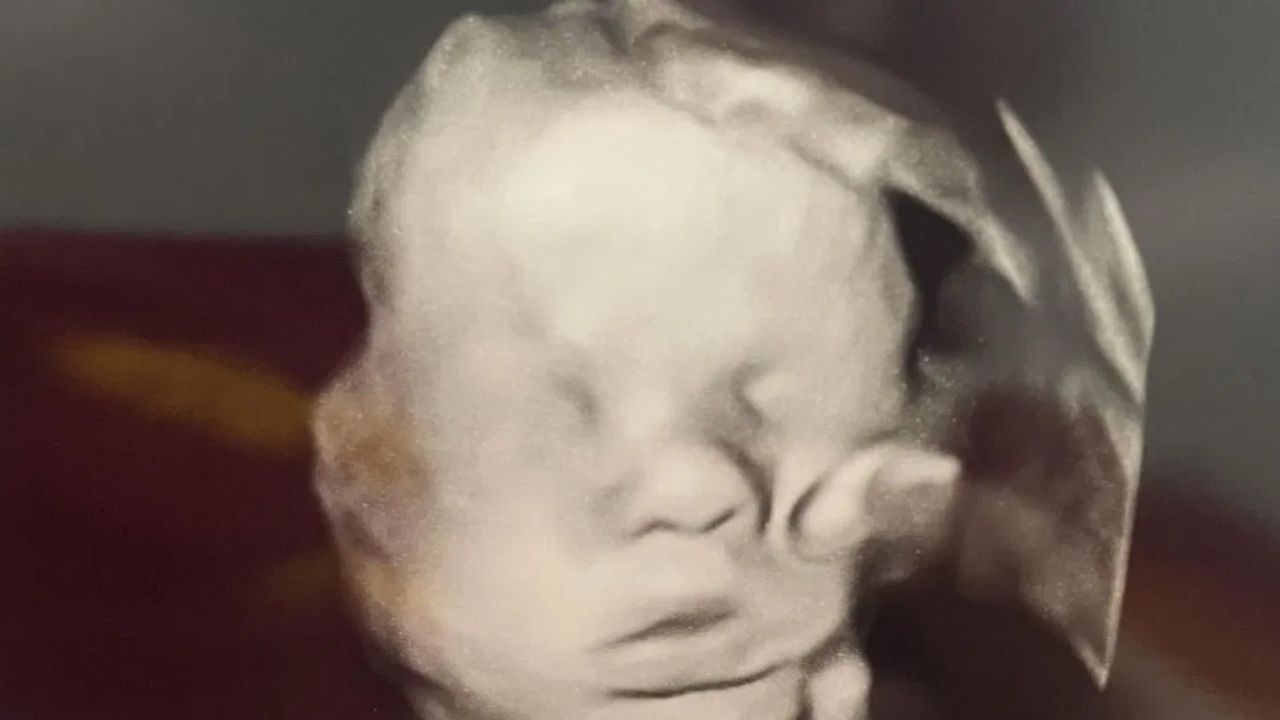

Amanda, uma mãe cristã de 33 anos no Kentucky (EUA), afirmou que, depois de ajoelhar-se em oração antes de um exame, viu — através de uma ultrassonografia em 3D — aquilo que descreveu como a mão de Deus repousando sobre a cabeça de seu bebê, com 32 semanas de gestação. Segundo o site MyCharisma, a primeira a notar o fenômeno foi a filha mais velha, Bailey, que perguntou inocentemente: “De quem é essa mão?”

A imagem viralizou nas redes, emocionando muitos fiéis e gerando debates entre crentes e céticos. Para Amanda, que já perdeu um filho ainda no ventre devido a uma doença rara, o momento teve duplo peso, de dor, superação e fé renovada. Ainda conforme o relato em MyCharisma, após ser avisada de uma possível anomalia cardíaca no bebê, ela intensificou suas orações pedindo que Deus mantivesse Sua mão protetora sobre ele.

Alguns especialistas, porém, oferecem uma explicação mais cética: essa suposta mão divina poderia se tratar de um artefato na imagem de ultrassom, uma ilusão causada por sombras, posicionamento fetal ou imperfeições no processo de renderização, o fenômeno psicológico conhecido como pareidolia.

Em Bored Panda, médicos explicam que o ultrassom é uma imagem construída por ecos e sombras e, por isso, suscetível a interpretações visuais humanas.

Apesar disso, Amanda e seu esposo Kyle veem no registro um sinal de que suas orações foram respondidas. Ela relatou que, em exames posteriores, a suposta anomalia cardíaca deixou de aparecer, o que fortaleceu ainda mais sua convicção de que Deus agiu em favor do bebê.